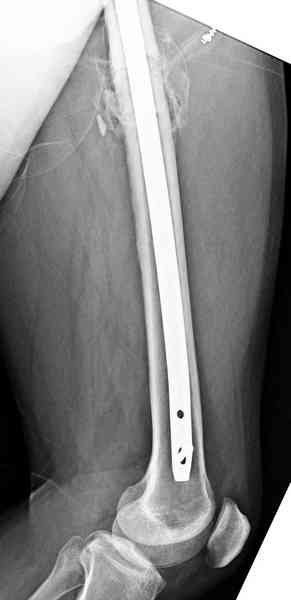

Здесь представлены снимки больного 65 лет, поступившего с диагнозом перелом

бедра после автоаварии.

В первый же день произведено антеградное штифтованием DePuy Trochanteric Nail.

Послеоперационные снимки